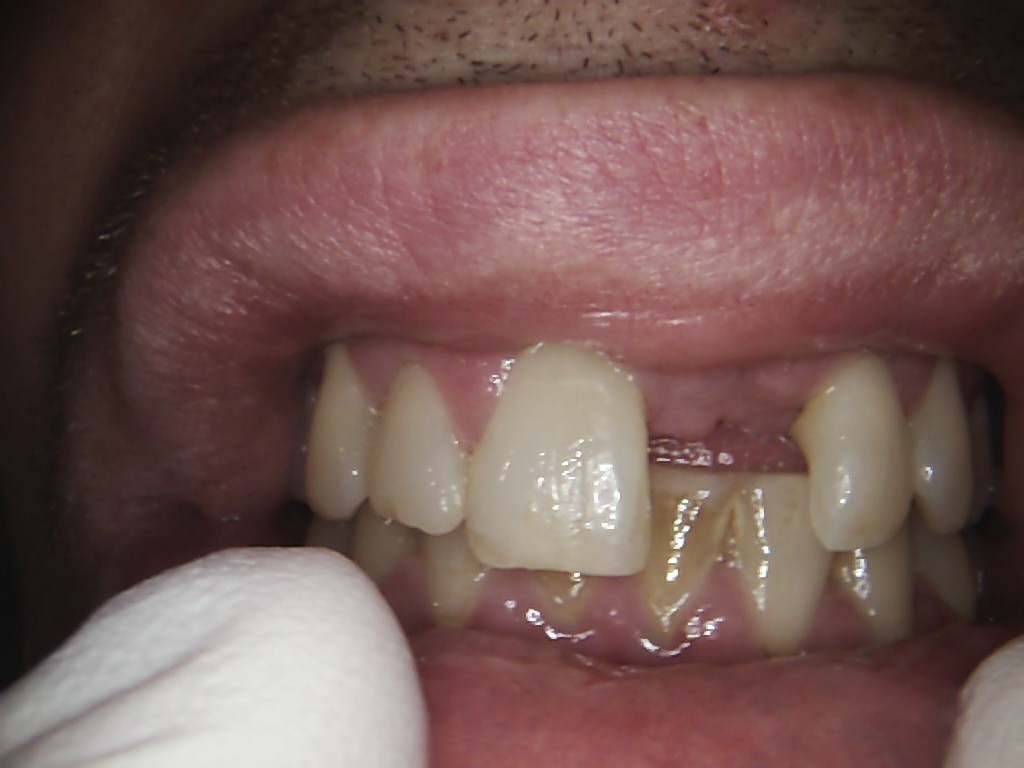

Examples of our work.

Single front tooth case